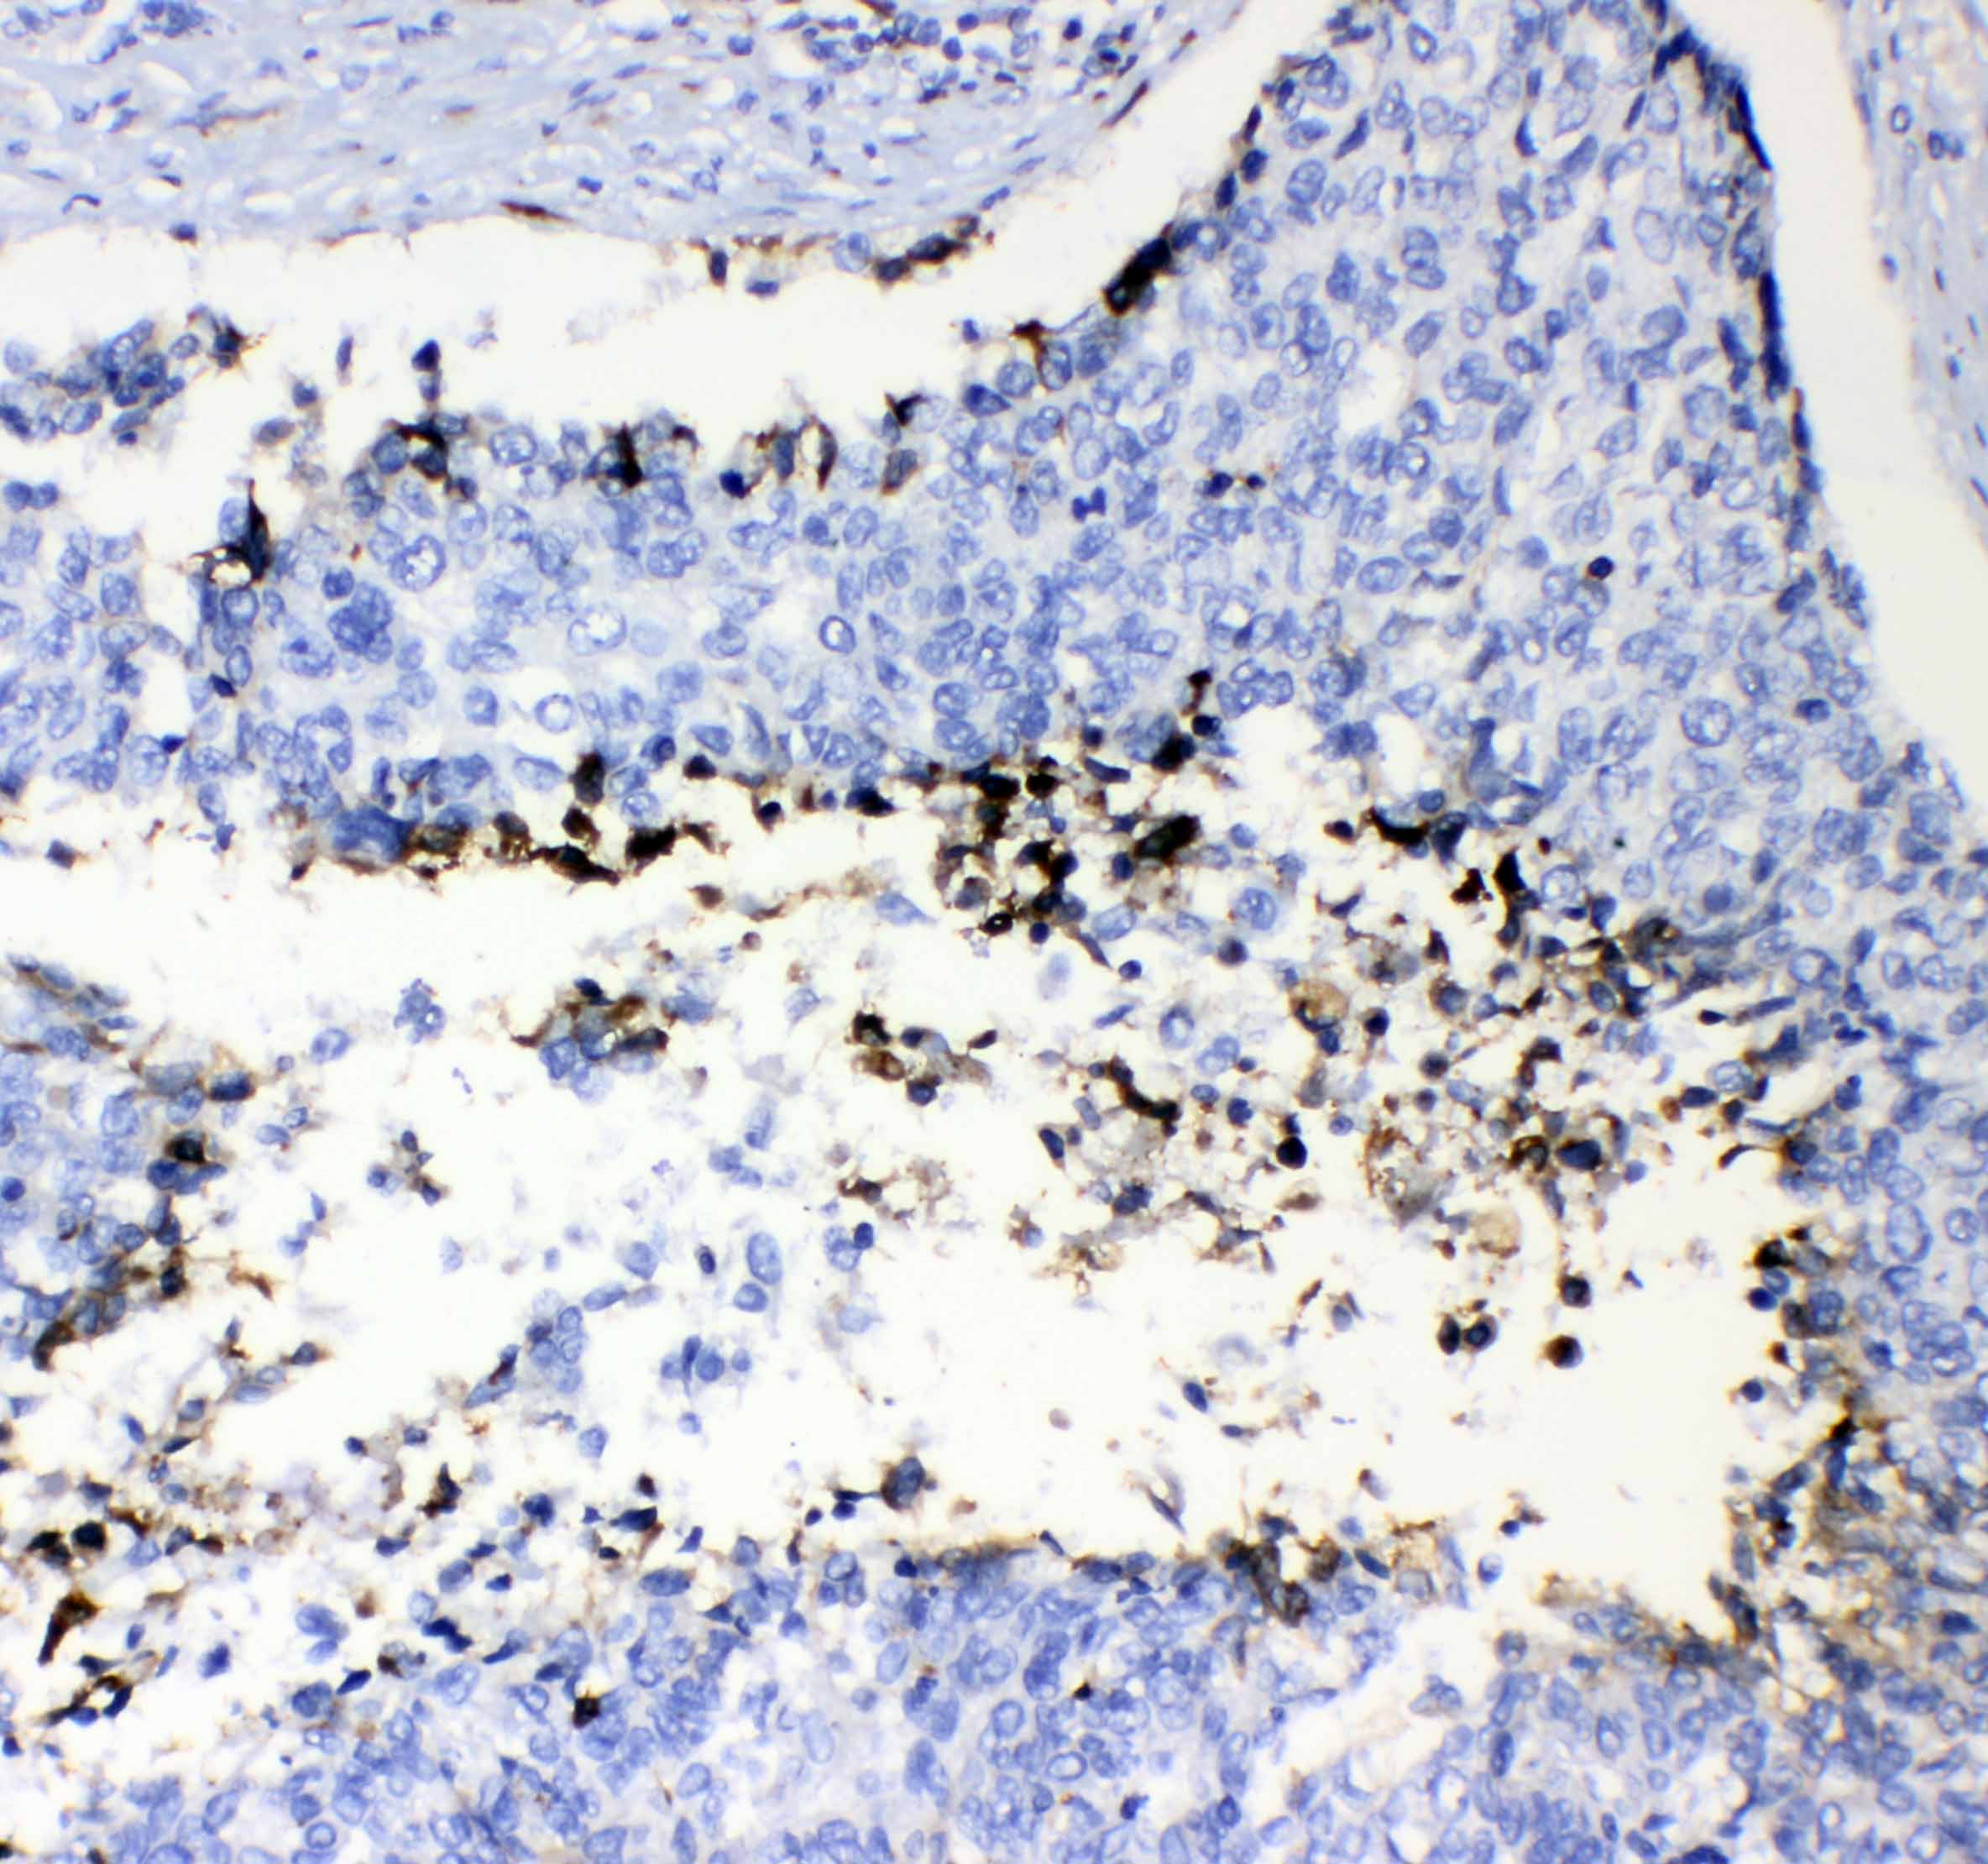

IHC analysis of F2 using anti-F2 antibody (A00044).

F2 was detected in a paraffin-embedded section of human lung cancer tissue. Biotinylated goat anti-rabbit IgG was used as secondary antibody. The tissue section was incubated with rabbit anti-F2 Antibody (A00044) at a dilution of 1:200 and developed using Strepavidin-Biotin-Complex (SABC) (Catalog # SA1022) with DAB (Catalog # AR1027) as the chromogen.